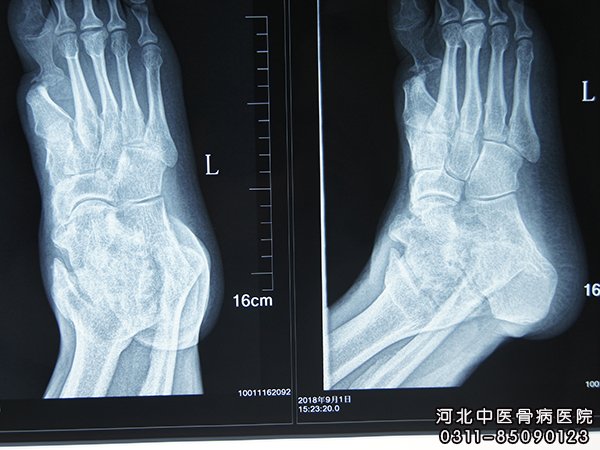

三、骨髓炎X线检查

骨髓炎的诊断方法还包括X线检查。X线变化在感染3~4周出现,表现为骨质不规则增厚和硬化,有残留的骨吸收区或空洞,其中可有大小不等的死骨,有时看不到骨髓腔。小骨腔和小死骨在硬化骨中有的不能显影,所以实际存在的数目往往比照片上所显示的多。